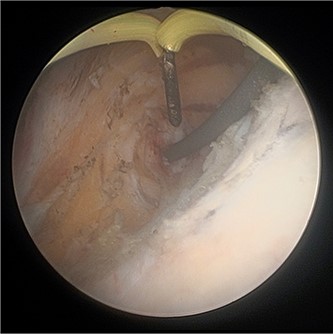

On both cases, under general or regional anaesthesia, a cystoscopy was performed and the interureteric bar was identified. A hybrid ‘sensor’ or ‘Terumo’ hydrophilic guidewire was advanced concurrently using the access from the existing nephrostomy tube with fluoroscopic assistance down to the level of the ureteric cul-de-sac. A combined visual- and x-ray-guided approach verified the exact location of the course of the intramural ureter, in correlation to the resectoscope and a Collins knife was used to incise the bladder mucosa (Fig. 2) above the level of the guidewire, on the virtual course of the intramural ureter exposing the intramural ureter. In all three attempts, the incision of bladder mucosa above the antegrade ureteric guidewire ended up with a successful identification of the guidewire, allowing access to the ureteric cul-de-sac. Stent graspers were used to snare the guidewire into the bladder (Fig. 3). With safety wire in place, management of the neo-orifice could then be performed.

A combined visual- and x-ray-guided approach verified the exact location of the course of the intravesical intramural right ureter, in correlation to the resectoscope. (A) X-ray, (B) cystoscopic view.